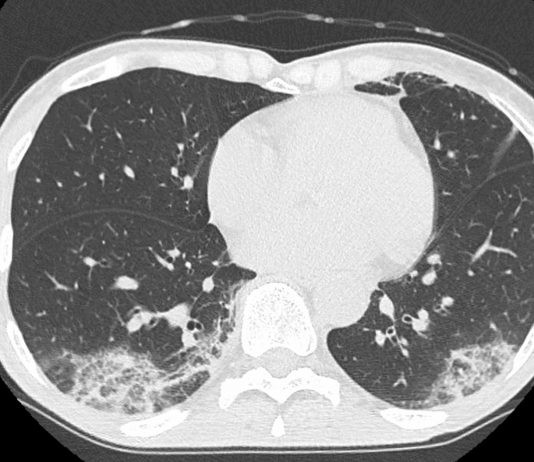

46-year-old asymptomatic female patient underwent chest radiography followed by CT since her husband was diagnosed of Covid-19 pneumonia (case n 14). pO2: 98%.